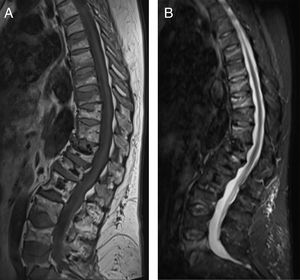

MétodosSe incluyeron 10 mujeres diagnosticadas de OP posmenopáusica que presentaron fracturas vertebrales múltiples tras suspender DMab, atendidas en el Servicio de Reumatología de un hospital español de tercer nivel entre 2015 y 2018. Las fracturas fueron diagnosticadas mediante radiología convencional y en alguno de los casos se realizó además resonancia magnética para aclarar su cronología. Se consideraron fracturas incidentes aquellas de un grado mayor o igual a I según la escala de Genant. Una vez confirmadas se estudiaron, de forma retrospectiva, parámetros demográficos, clínicos, analíticos y densitométricos.

ResultadosLas características de las pacientes se muestran en la tabla 1. La edad media al inicio del tratamiento fue de 66±7,7 años. Cuatro pacientes tenían historia previa de fracturas por fragilidad y solo una tenía factores de riesgo de OP secundaria (inhibidores de la aromatasa, caso 7). Nueve pacientes (90%) habían recibido otros tratamientos previos al inicio de DMab (7 bisfosfonatos orales, 5 ranelato de estroncio, 2 raloxifeno, 1 tibolona y 1 calcitonina). Las pacientes recibieron entre 3 y 9 dosis de DMab, siguiendo la posología recomendada en ficha técnica, con una media de 6±1,7. El motivo de retirada del fármaco fue manipulación dental (casos 1 y 6), bajo riesgo de fractura (caso 5) y cumplimiento del tiempo estimado por el médico prescriptor. En todos los casos salvo en dos se había realizado una densitometría ósea previa al inicio de DMab. La media de T-score antes del tratamiento fue -2,6±0,6 en cuello femoral (CF) y -3,0±1,3 en columna lumbar (CL). Asimismo, en todos los casos salvo en dos (casos 7 y 9) se realizó densitometría transcurridos al menos 6 meses tras la retirada del tratamiento, con una media de T-score -3,2±0,7 en CF y -3,2±1,6 en CL. Los marcadores de recambio óseo tras al menos 10 meses de la suspensión se objetivaron elevados con una media de telopéptico del colágeno (CTX) de 1,32±0,32 ng/ml y de propéptido del colágeno (P1NP) de 181,6±104,1 ng/ml. El tiempo transcurrido entre la última dosis del fármaco y la aparición de la primera fractura varió entre 8 y 18 meses, con una media de 10,9±3,3 meses. Las pacientes presentaron entre 2 y 9 fracturas, registrándose un total de 49 fracturas. En la figura 1 se muestran las pruebas de imagen diagnósticas del caso 10. En todos los casos ocurrieron de forma espontánea, sin traumatismo asociado. Las vértebras más afectadas fueron L3, L5, D6, D7, D9 y D11. A dos pacientes (casos 1 y 2) se les realizó vertebroplastia, produciéndose en ambas nuevas fracturas vertebrales. En una paciente (caso 9) se inició alendronato seis meses después de suspender DMab siguiendo las recomendaciones de la European Calcified Tissue Society (ECTS) y pese a ello presentó fracturas vertebrales (fig. 2). Con respecto al tratamiento farmacológico recibido tras las fracturas, las opciones más utilizadas fueron teriparatida (30%), bisfosfonatos orales (20%) y DMab (20%).